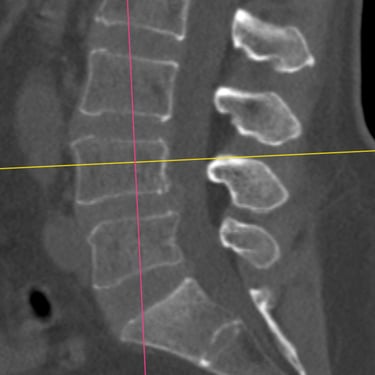

Listesis Lumbar: Artrodesis con Tornillos Transpediculares y Fusión Intersomática Transforaminal (TLIF).

La listesis lumbar es el deslizamiento anormal de una vértebra sobre otra, lo que puede generar dolor lumbar crónico, inestabilidad y compresión de las raíces nerviosas. Cuando el tratamiento conservador no es suficiente, la artrodesis con tornillos transpediculares (FTP) asociada a la fusión intersomática transforaminal (TLIF) es una técnica quirúrgica efectiva. Este procedimiento permite estabilizar la columna, restaurar la alineación vertebral y lograr una fusión sólida, al mismo tiempo que descomprime las estructuras nerviosas. La combinación de estas técnicas mejora el control del dolor, la función neurológica y la calidad de vida del paciente.